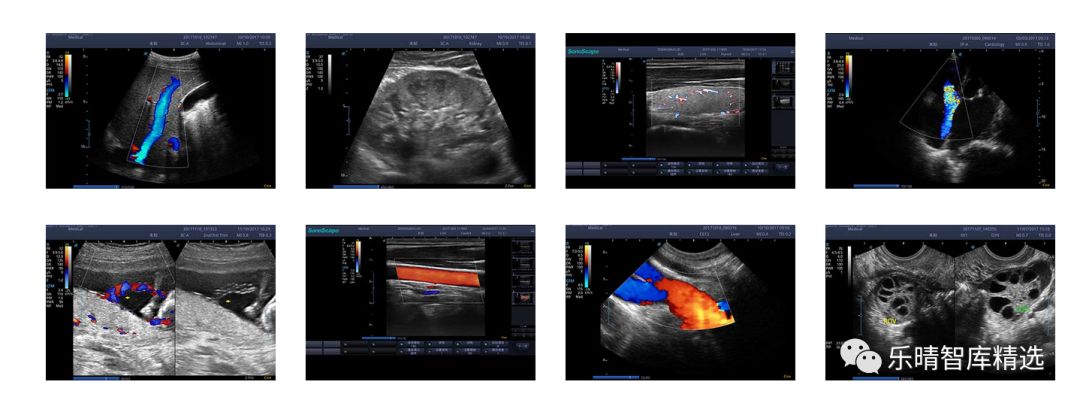

从传统的形态学诊断发展到功能诊断,如弹性成像、组织斑点追踪、超声造影、微观研究等。

比如超高端的心脏彩超,在二维图像和彩色血流信息的基础之上,某些进口企业把特殊分析软件加在彩超里面,包括心肌运动、心脏在有局限性的梗死的状态下、心肌功能的衰退等,机器诊断的层面就是由单纯的图像诊断上升到一个功能诊断,行业出现了质的飞跃。

随着超声应用领域的逐步拓展,满足不同临床需求的特定超声不断出现,超声的应用场景日渐丰富,“超声+”的概念成为主流。

迈瑞的DC-8、R7等型号,开立的S50均已达到中高端水平,基本可以满足临床科室的基本需求,媲美进口品牌,在同档次的较量中,国产品牌功能更加丰富、产品性能更高、性价比更具优势,作为进口替代的基础要素——产品性能已经具备,中高端市场的进口替代正在全面铺开。